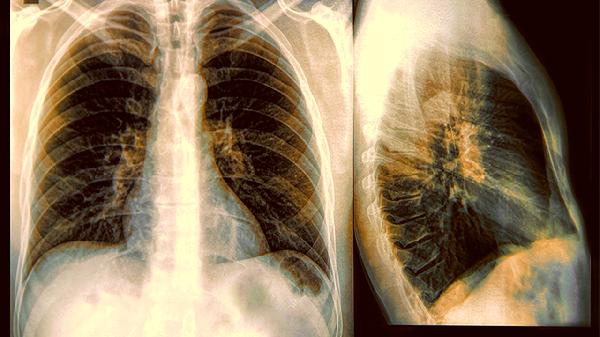

部分治疗关节炎、心脏病的药物可能引发肺纤维化。如果用药后出现不明原因干咳,建议拍个胸片检查。